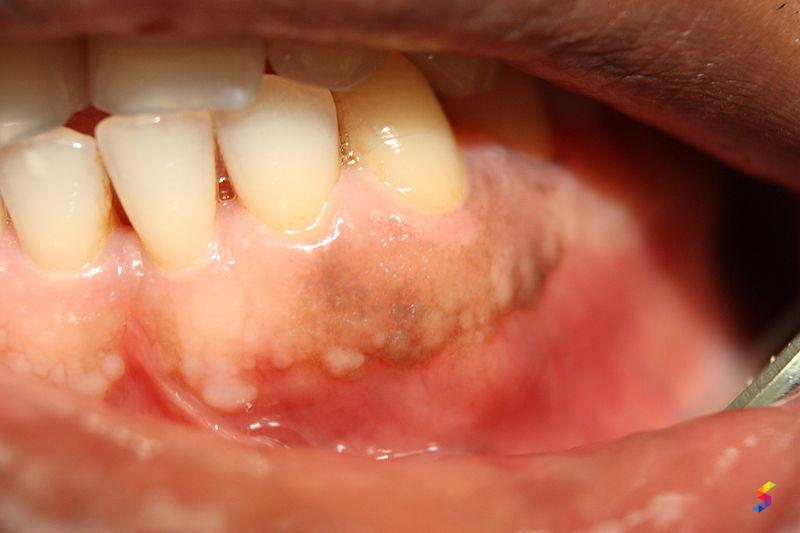

Gingivitis Examples . Gingivitis is caused by bacterial plaque (dental biofilm) that accumulates daily on the teeth. Common symptoms include red, swollen, bleeding gums. But it might spread to the periodontium (the soft tissue and bone that support our teeth). Gingivitis results most often from. It happens when plaque and bacteria build up on your teeth and cause infection. The most common culprit for gingivitis is dental plaque. There are various forms of gingivitis based on clinical appearance, duration of infection, severity, and etiology. However, the chronic form of gingivitis that is caused by. Results in redness, slight swelling, or. Gingivitis is the earliest stage of gum disease. Gingivitis is a mild form of periodontal disease characterized by inflammation of the gums (gingivae). A gum inflammation (gingivitis) is usually harmless and goes away quickly.